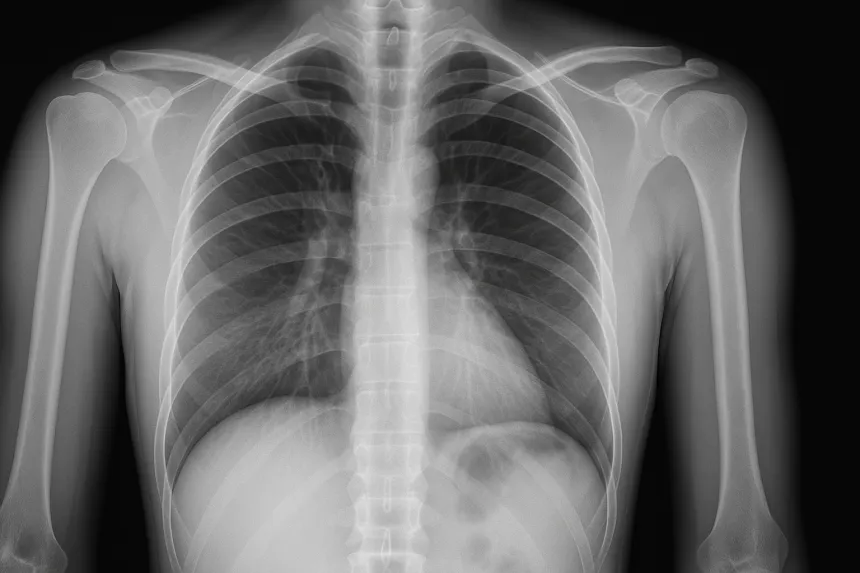

필요한 경우 흉부 X-ray, 흉추 MRI, CT 등을 통해 심장질환, 폐질환, 척추질환을 감별합니다.